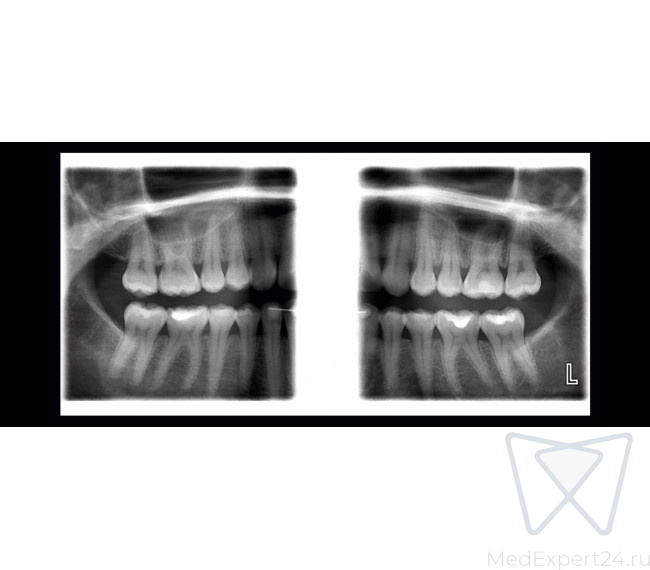

Planmeca ProOne - это полнофункциональный панорамный рентгеновский аппарат, работающий полностью в цифровом формате. Благодаря передовым инновациям, он сочетает в себе большие диагностические возможности и превосходное качество изображения в компактном и простом в использовании аппарате. Широкий выбор программ облучения и параметров графического интерфейса для пользователя гарантируют, что рентгенологические исследования всех видов выполняются очень быстро и без каких-либо усилий. Будучи небольшого размера, установка Planmeca ProOne предоставляет все преимущества цифрового изображения.

6 стандартных программ:

- Расширенный пакет панорамных программ:

- Межпроксимальная панорамная

- Ортогональная (перио) панорамная

- Боковой задне-передний ВНЧС

- Задне-передние пазухи без вращения

- Кросс-секции

- Прикусная панорамная